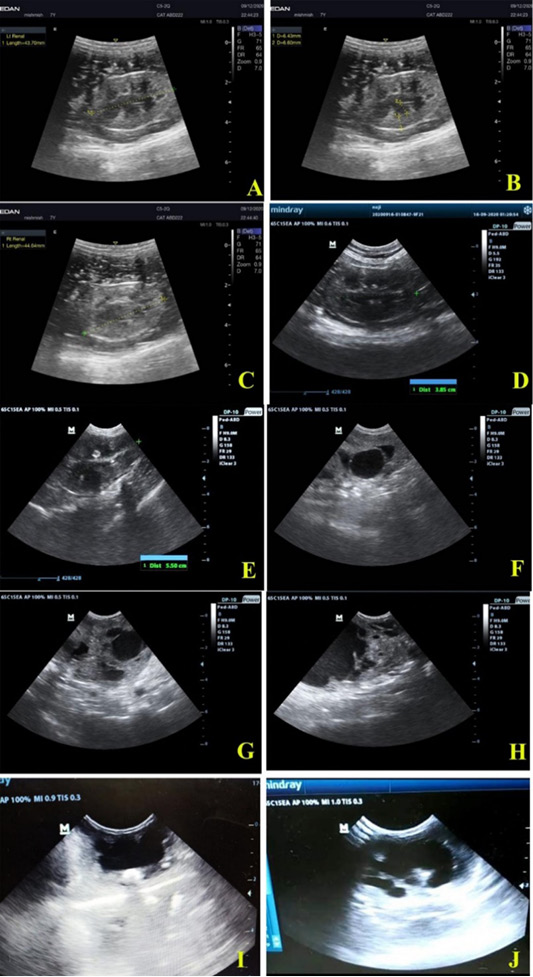

Ultrasonographic views of healthy feline kidneys showing. A, Left kidney with length 4.37 cm; B, left renal cortex (0.64 cm), renal medulla (0.66 cm); C, right kidney length 4.46 cm; D, left kidney of another cat with length 3.85 cm. Feline unilateral hydronephrosis cases showing; E, enlarged right kidney (5.50 cm length); F, loss of architecture and dilated renal pelvis of right kidney in two years old mixed breed tomcat; G and H, loss of echotexture with multiple diverticuli in right kidney of 1 year old mixed breed queen; I, severe dilation of renal pelvis with thinning of renal cortex and medulla; J, massive loss of architecture with normal dimensional left kidney in 3 months old tomcat.